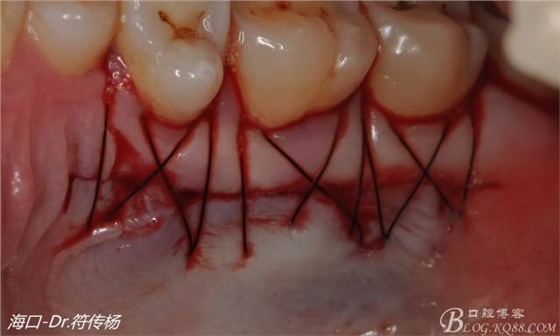

腭部使用水平懸吊縫合更利于壓迫止血

受植區(qū)建議使用雙交叉垂直懸吊縫合術(shù)來(lái)固定結(jié)締組織并能讓齦瓣更貼合根面利于術(shù)后一期愈合